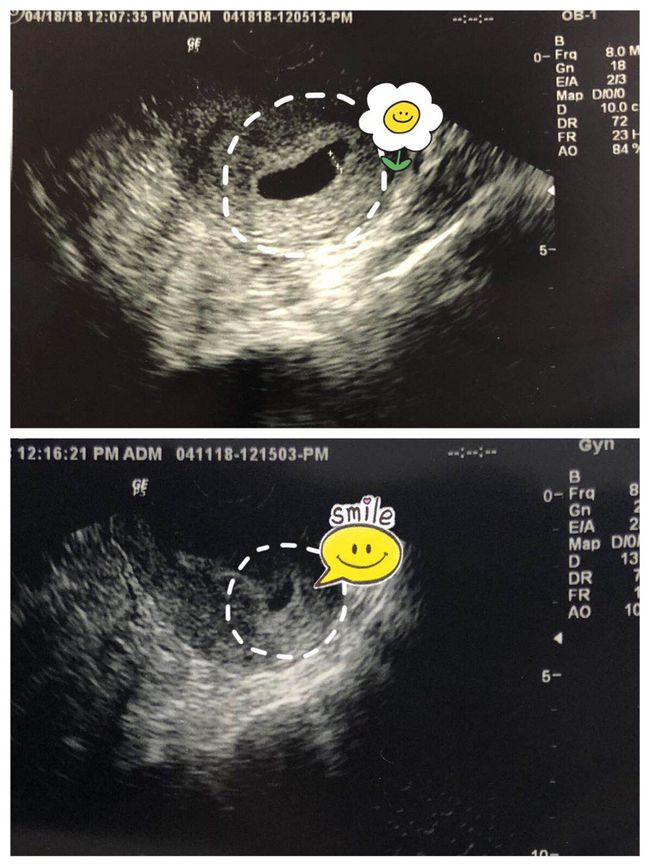

5. 子宫内节育器(IUD)

子宫内节育器是一种长效避孕工具,它可以在医生的指导下放置在子宫内,通过释放激素或物理阻挡来阻止怀孕。IUD的避孕效果非常好,可以持续几年,但需要定期检查和维护。